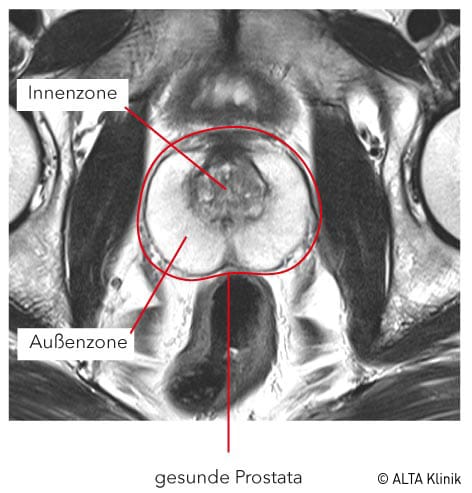

Auf den MRT-Bildern ist ein Prostatakrebs von gesunden Gewebestrukturen abgrenzbar.

Diese Veränderung der Prostata wird als eine altersbedingte und gutartige Erkrankung bezeichnet, die sogenannte benigne Prostatahyperplasie. Dabei wachsen gutartige Knoten (Adenome) in der Innenzone und verschmälern dadurch die Außenzone der Prostata.

mpMRT der Prostata bei Prostatakrebs und Prostatavergrößerung